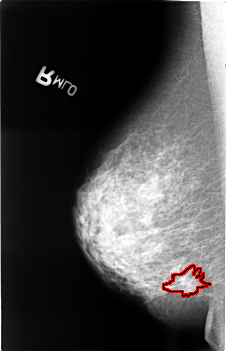

B_3399_1.LEFT_CC

LEFT_CC LINES 4528 PIXELS_PER_LINE 2880 BITS_PER_PIXEL 12 RESOLUTION 50 NON_OVERLAY

LEFT_MLO LINES 4552 PIXELS_PER_LINE 2888 BITS_PER_PIXEL 12 RESOLUTION 50 NON_OVERLAY

FILE: B_3399_1.RIGHT_CC.OVERLAY

TOTAL_ABNORMALITIES 1

ABNORMALITY 1

LESION_TYPE CALCIFICATION TYPE PUNCTATE DISTRIBUTION CLUSTERED

LESION_TYPE MASS SHAPE ARCHITECTURAL_DISTORTION MARGINS ILL_DEFINED-SPICULATED

ASSESSMENT 4

SUBTLETY 3

PATHOLOGY MALIGNANT

TOTAL_OUTLINES 1

BOUNDARY